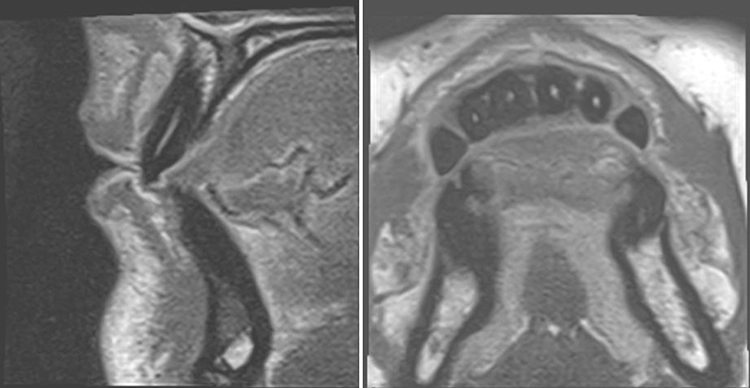

Die Magnetresonanztomographie (MRT) ist in der Medizin seit vielen Jahren etabliert und erobert dort mit unzähligen, jährlich zunehmenden Optionen und Sequenzen immer weitere Anwendungen. Damit übertrifft die MRT in der Medizin deutlich alle anderen In-vivo-Bildgebungsarten im menschlichen Körper ohne invasive Eingriffe und ionisierende Strahlung [7]. Aufgrund neuer hardware- und softwareseitiger Entwicklungen ist sie im letzten Jahrzehnt auch zunehmend für Anwendungen in der Zahn-, Mund- und Kieferheilkunde interessant geworden [8] (Abb. 3).

Im Jahr 2023 stellte Siemens in Kooperation mit Sirona ein Projekt für ein „dental dedicated MRT“ vor, bei dem ein speziell für die zahnmedizinischen Anforderungen maßgeschneidertes MRT entwickelt und auf den Markt gebracht werden soll.** Hier spielen die neuen technischen Möglichkeiten in der möglichen Größenreduktion und auch in reduzierten hardwareseitigen Anforderungen eine Rolle. Eine Arbeitsgruppe aus Aarhus betreibt bereits ein prototypisches Gerät [10]. Einige Aufnahmen dieses Prototyps sind in den Abbildungen 4 und 5 zu sehen. Das Gerät wurde auf der Konferenz der European Academy of Dentomaxillofacial Radiology (EADMFR) vom 12. bis 15. Juni 2024 offiziell vorgestellt.***